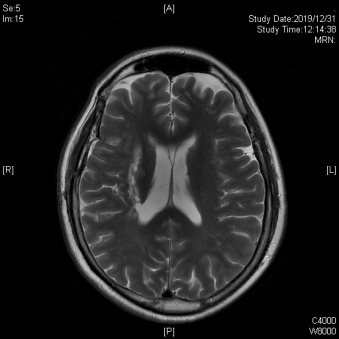

康复团队首先通过脑功能磁共振和脑电图检查了解王阿姨的脑功能情况,并进行了专业而详尽的功能评估。随后给王阿姨戴上脑电帽,将瘫痪的左足放入康复机器人足托。根据电脑提示,王阿姨集中精力想象左踝关节背屈动作。而康复机器人将根据王阿姨的脑电运动意图信息完成一次背屈动作。发现自己的运动信号能指挥机器运动,王阿姨非常欣喜。随后按照治疗计划,王阿姨每天在常规康复训练基础上配合1小时的脑机接口足踝康复机器人训练。经过近1个月的治疗,王阿姨左侧踝关节由完全瘫软,逐渐看到肌肉收缩,踝背屈动作越来越明显,随之而来的是站立、行走功能也在迅速提高。现在的王阿姨虽然步行速度还比较慢,但已经基本恢复了独立站立,行走能力。

王阿姨脑磁共振影像